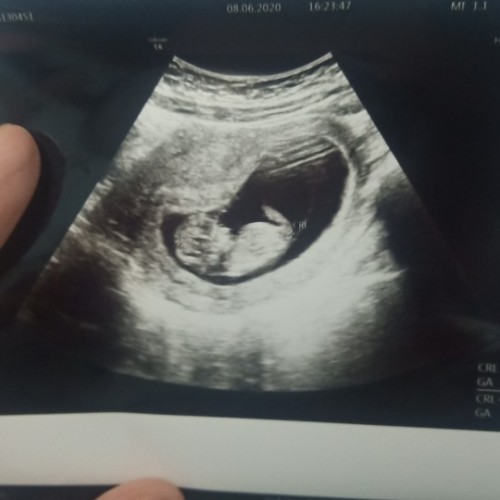

10สัปดาห์เป็นตัวแล้วค่ะ

ของเราซาวด์ตอน9สัปดาห์